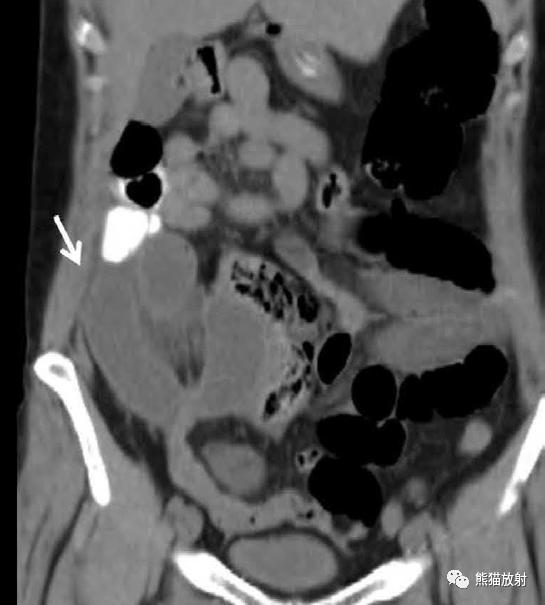

肠系膜囊性淋巴管瘤 。增强CT示右腹部多房囊性肿块,可见菲薄分隔,占据小肠系膜。